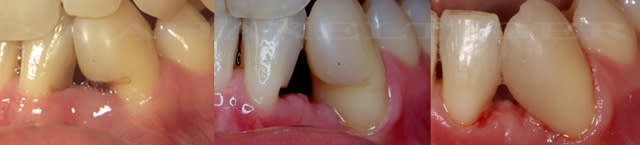

une attaque parodontal maousse.... et absence totale de gencive attachée sur une 35.

voilà à quoi ça ressemble aujourd'hui...